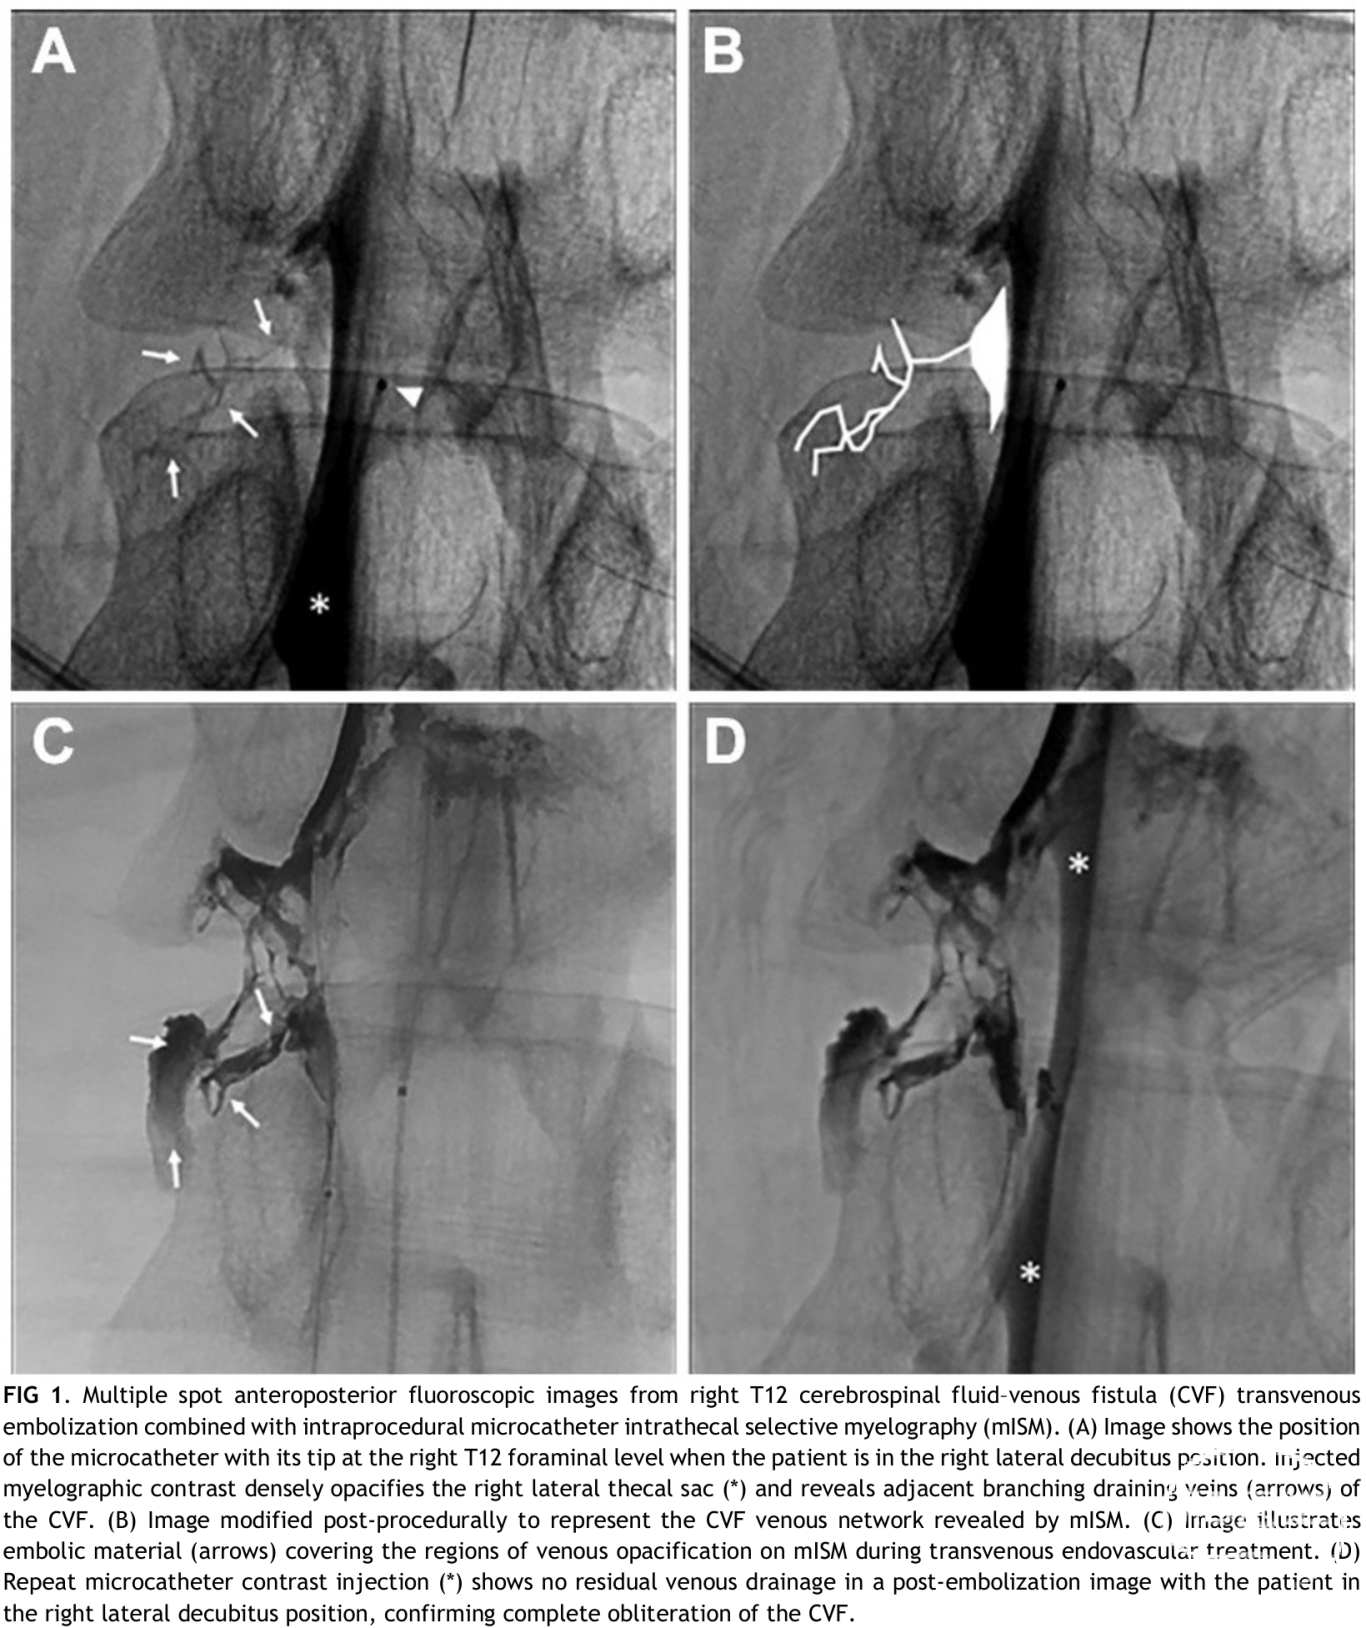

● mISM(microcatheter intrathecal selective myelography,微导管鞘内选择性脊髓造影)是一种术中荧光透视下经微导管鞘内靶向注射造影剂的技术,可在同一介入流程里实时确认脑脊液-静脉瘘(CVF)位置、描绘引流静脉图谱,并即刻验证栓塞后瘘口是否完全闭塞。

● 适用场景:主要用于CVF血管内栓塞术的术中实时评估,包括术前瘘口确认、术中解剖导航、术后闭塞效果验证,实现“诊断-治疗-验证”单疗程完成。

● 成像体位:右侧卧位获取T12水平正前后位荧光影像,术前、术后采用相同参数成像以对比。

● 联合治疗:造影确认后患者改仰卧位,经腰升静脉入路用Onyx-18进行经静脉栓塞,术中参考术前造影图谱确保栓塞剂覆盖引流静脉网络。

● 精准导航:清晰显示CVF引流静脉分支网络,为栓塞剂靶向递送提供高分辨率图谱,避免遗漏病变血管。

● 术后即刻验证:栓塞后可即时造影确认瘘口完全闭塞,减少术后延迟影像学检查需求。

● 低流量CVF:可通过生理盐水冲洗微导管提升检出敏感性,或联合DSM技术优化显影效果。● 疗效验证:本例54岁复发性自发性颅内低压(SIH)患者,术后即刻头痛缓解,1个月随访症状持续改善,术后造影显示CVF完全闭塞(无残留静脉显影)。